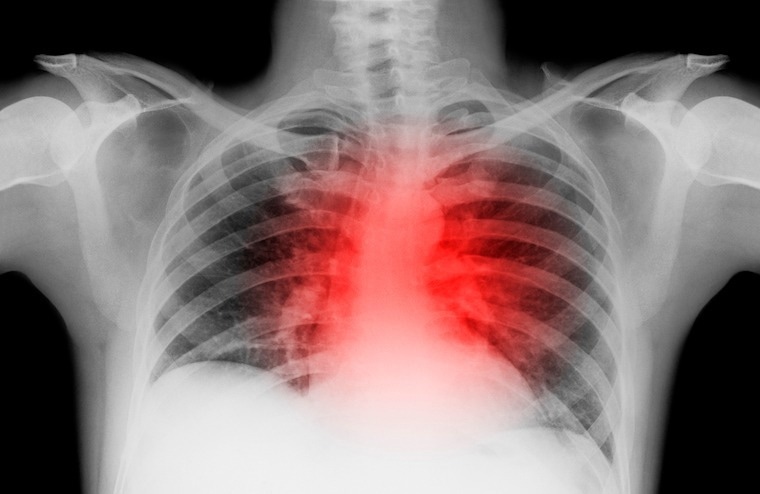

In heart failure, the organ loses the ability to pump adequate blood for the body's needs. This can lead to fatigue, wheezing, weakness, swollen legs and feet and, ultimately, death. Image Credit: UVA Health

In heart failure, the organ loses the ability to pump adequate blood for the body's needs. This can lead to fatigue, wheezing, weakness, swollen legs and feet and, ultimately, death. Image Credit: UVA Health

Heart failure is a progressive condition – meaning it grows worse with time – in which the heart loses the ability to pump blood. This can lead to fatigue, wheezing, weakness, swollen legs and feet and, ultimately, death.